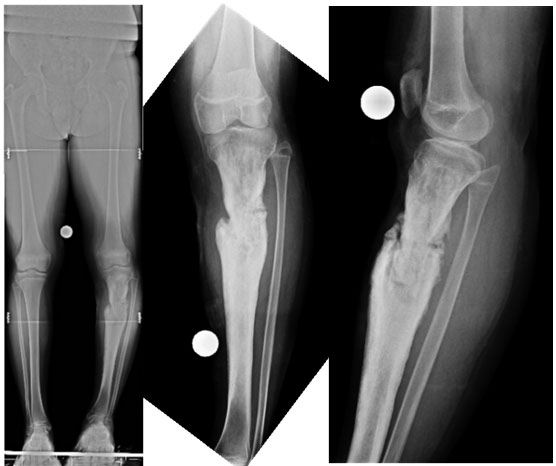

| At Presentation |

| 15 year old boy, presented with mobile nonunion of upper 1/3rd of tibia of 7 months duration. He had developed a pathological fracture secondary to osteomyelitis which was secondary to a previous surgery for hematoma evacuation. There was no sign of an active infection on presentation. |